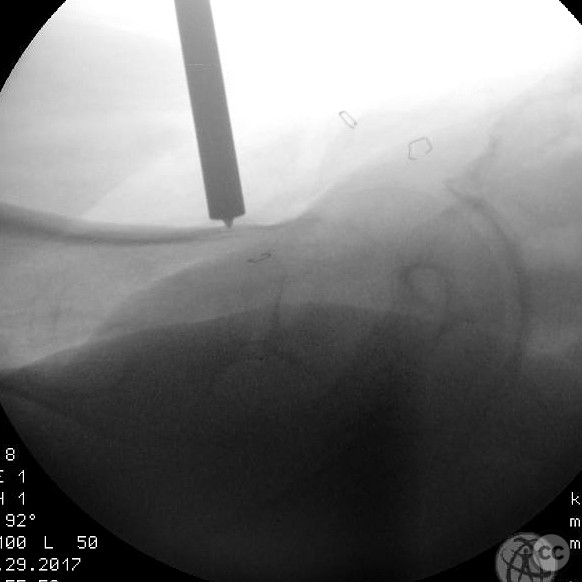

Patient positioning:  The patient was positioned supine on a fracture table to facilitate closed reduction and percutaneous fixation under fluoroscopic guidance.

Anatomical surgical approach:  A percutaneous approach was utilized, involving small stab incisions for the insertion of guide wires and cannulated screws. Fluoroscopic imaging was employed to ensure proper alignment and fixation.